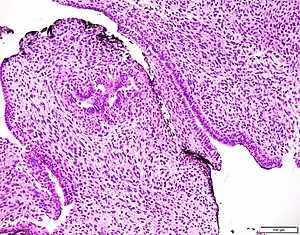

| Prostatic stromal tumour of uncertain malignant potential. H&E stain. | |

Prostatic stromal tumour of uncertain malignant potential (PSTUMP) is a rare tumour of the prostate gland stroma that may behave benign or like cancer.